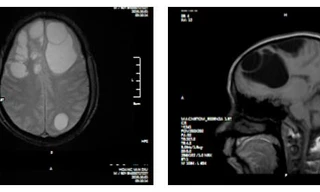

TPO - Người bệnh Hoàng Văn D (nam giới, 50 tuổi, Lào Cai), người bệnh được chuyển tuyến từ bệnh viện tỉnh Lào Cai xuống Bệnh viện đa khoa tỉnh Phú Thọ ngày 04/10/2019 trong tình trạng giảm trí nhớ, giảm tri giác.